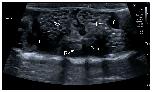

Figure 6. HR-US image of a female Kaloula pulchra obtained in the transverse plane using a ventral acoustic window. The image was taken just after oviposition. Both ovaries (right ovary: Ro; left ovary: Lo) appeared as hyperechoic structures with multiple hypoechoic foci which represent follicles. The kidneys are also visible (right kidney: Rk; left kidney: Lk). This animal had free fluid (f), which is considered normal in amphibians. The fluid around the ovaries improves its margin definition. |